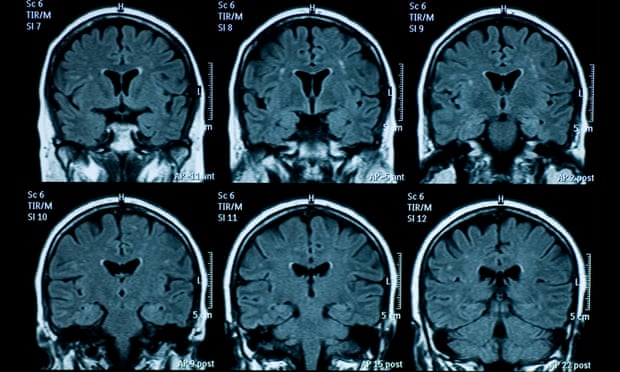

Theo trang The Guardian (Anh), các nhà nghiên cứu đã chụp ảnh cộng hưởng từ (MRI) của 81 thanh thiếu niên ở Mỹ trước đại dịch (từ tháng 11/2016 đến tháng 11/2019), và so sánh với ảnh chụp MRI của 82 thanh thiếu niên trong thời gian đại dịch bùng phát, nhưng là sau khi dỡ bỏ lệnh phong toả (dữ liệu được thu thập từ tháng 10/2020 đến tháng 3/2022).

Cụ thể, so với trước đại dịch, nhóm thanh thiếu niên ở giai đoạn hậu phong tỏa có vỏ não mỏng đi và sự phát triển của vùng hồi hải mã và hạch hạnh nhân lớn hơn. Điều này cho thấy các quá trình phát triển não đã tăng tốc. Nói cách khác, bộ não của họ đã già đi nhanh hơn.

Sự khác biệt về tuổi của não bộ là khoảng 3 năm. Ảnh: Getty Images